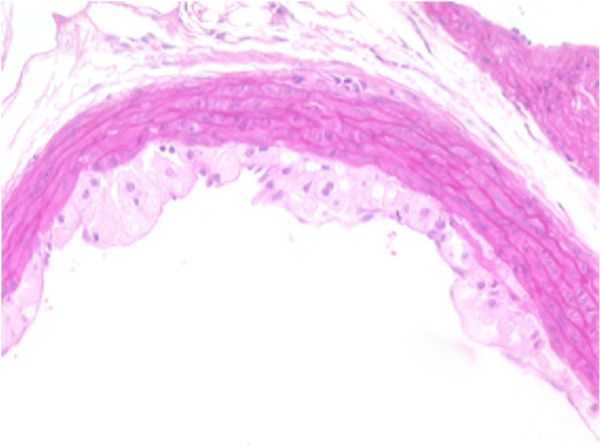

Aorta-b

AORTA–b: F19-01

Atherosclerotic plaque, tunica intima/media, thoracic aorta.

Presented with a segment of arterial wall that exhibits a mild, focally-extensive compression of the tunica media by opposing accumulations of eosinophilic, foamy, or lipid appearing material situated within the subendothelial space of the tunica intima and the tunica adventitia. An early, minimal to mild fibroplasia is evident in these areas within both the tunica intima and tunica adventitia. The endothelium is elevated by this material occupying the subendothelial space.